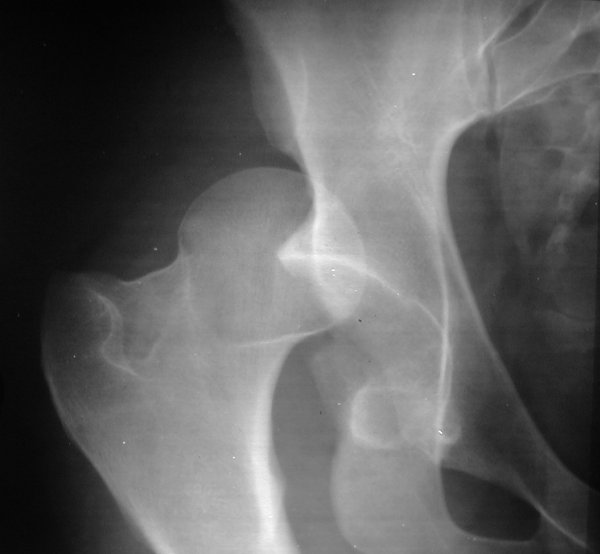

Return to Hip Fracture-Dislocation